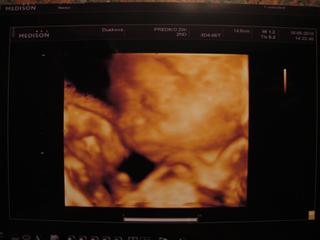

ahoj holky.tak máme za sebou 3D ultrazvuk a Filípek tam sebou opět mrskal že se nedala moc udělat pěkná fotečka ale měla sem radost jak už je krásné miminečko.už to šlo tak krásně všechno vidět.mám z něj radost jaky je šikulka.dokonce všichni usoudili že je celý tatínek 😀 a podle nosíka je.doktorka nam ho chvíli pustila na obrazovce tak sme se trošku zase mohli pokochat.sice sem to nemohla líp nafotit ale aspon něco 🙂 .něřekla nic ,tak si myslím že je všechno v pořádku i nadále.

Vidím tu fotečku Petrosčina Filípka 🙂 🙂 Moc krásný chlapeček 🙂 🙂 🙂 Gratuluji, UTZ jste si jistě moc užili 😉 🙂 😵

Petři no krásný bobášek🙂)))

Petrosko fotka je krásnááá 🙂

sarlot no byli sme tam asi 5 min jen.najela na miminko a hledala vhodné polohy na fotečku tak sme sem tam kukali jak tam chudáček bojuje.uplně ji do toho přístroje kopal,asi se mu to nelíbí když ho mačkala.ale moc sme si to neužili ale aspon chvilinku sme něco viděli.ale z fotečky jsem celkem sklamaná,za 200 a nic moc.na obrazovce byl prcek krásnější ale su ráda že sem aspon chvilkama kukala jak se tam vrtí.snad bude i nadále v pořádku.ale zajdu tam asi i ten 30 týden pokud mi má doktr neudělá do té doby sama ultr 😠